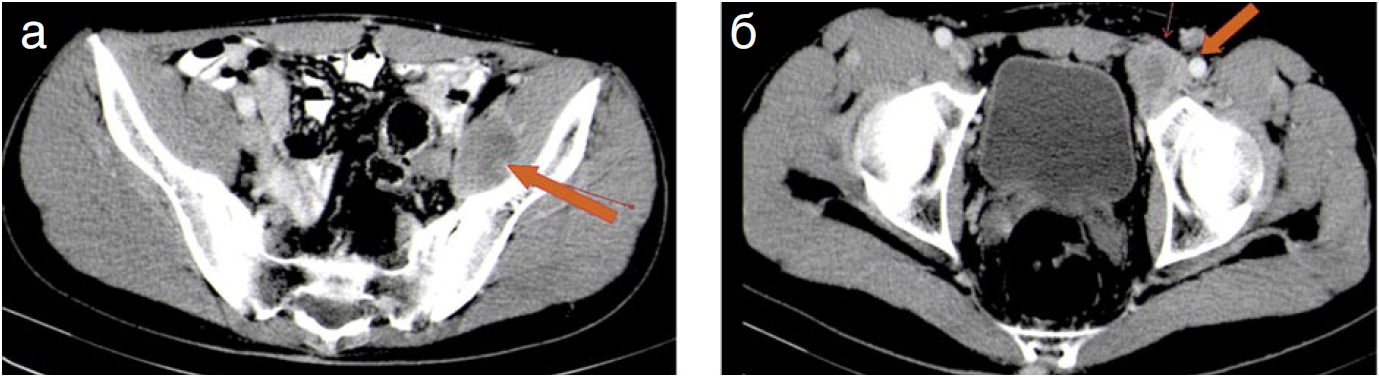

Через 4 мес после операции выялен 2-й рецидив заболевания: по данным КТ-ангиографии опухолевый узел тесно прилежит к наружным подвздошным сосудам слева, при этом нет четкой границы с наружной подвздошной веной на протяжении около 2 см, инфильтрирует косую мышцу живота, тесно прилежит к левой лонной кости, без признаков деструкции коркового слоя. Слева от узла отмечается инфильтрация клетчатки размером до 2×1,5 см, которая муфтообразно охватывает 1/2 окружности бедренной вены и артерии. Пресакрально слева, на уровне S1-позвонка (в зоне операции), сохраняется уплотнение клетчатки до 2,3×1,5 см – без динамики – послеоперационные изменения? (рис. 4).

Рис. 4. Пациент С. Через 4 мес после 2-й операции. КТ. Аксиальные срезы. Артериальная фаза. По ходу левых наружных подвздошных сосудов (а) и в проекции пахового канала (б) определяются рецидивные гиповаскулярные опухолевые узлы округлой формы с частично четкими контурами.

Fig. 4. Patient S. 4 months after the second surgery. CT. Arterial phase axial. Recurrent hypovascular tumor nodes round-shaped with partially sharp edges are observed along the left external iliac vessels (a) and in the projection of the inguinal canal (b).

15.11.2017 больной оперирован по поводу 2-го рецидива опухоли. Опухоль мобилизована от левой наружной подвздошной артерии и протеза левой общей бедренной артерии, левой бедренной вены, выполнена резекция наружной и внутренней косых мышц живота, надкостницы лонной кости. Послеоперационный период – без осложнений. При морфологическом исследовании – рецидив десмоидной опухоли с R1-краями резекции.